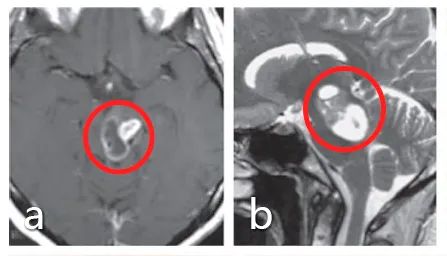

30岁女士,有复视和轻微右侧偏瘫,a、b图患者术前MRI显示中脑肿瘤,患者最初接受立体定向囊肿抽吸和间质放疗,并被诊断为毛细胞型星形细胞瘤,但肿瘤仍在生长。

巴教授为其手术,无手术并发症,f图显示伤口愈合正常,患者预后良好,无神经功能缺损。组织病理学检查为1级毛细胞型星形细胞瘤。g、h图术后MRI影像显示,肿瘤全切。随访MRI记录手术后9年无肿瘤复发。